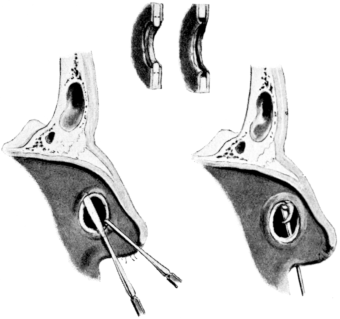

| 190. | Lines of Incisions in Intratympanic Operations | 341 |

| 191. | Cutting through Intratympanic Adhesions | 344 |

| 192. | Free Edge of Tympanic Membrane cut through | 344 |